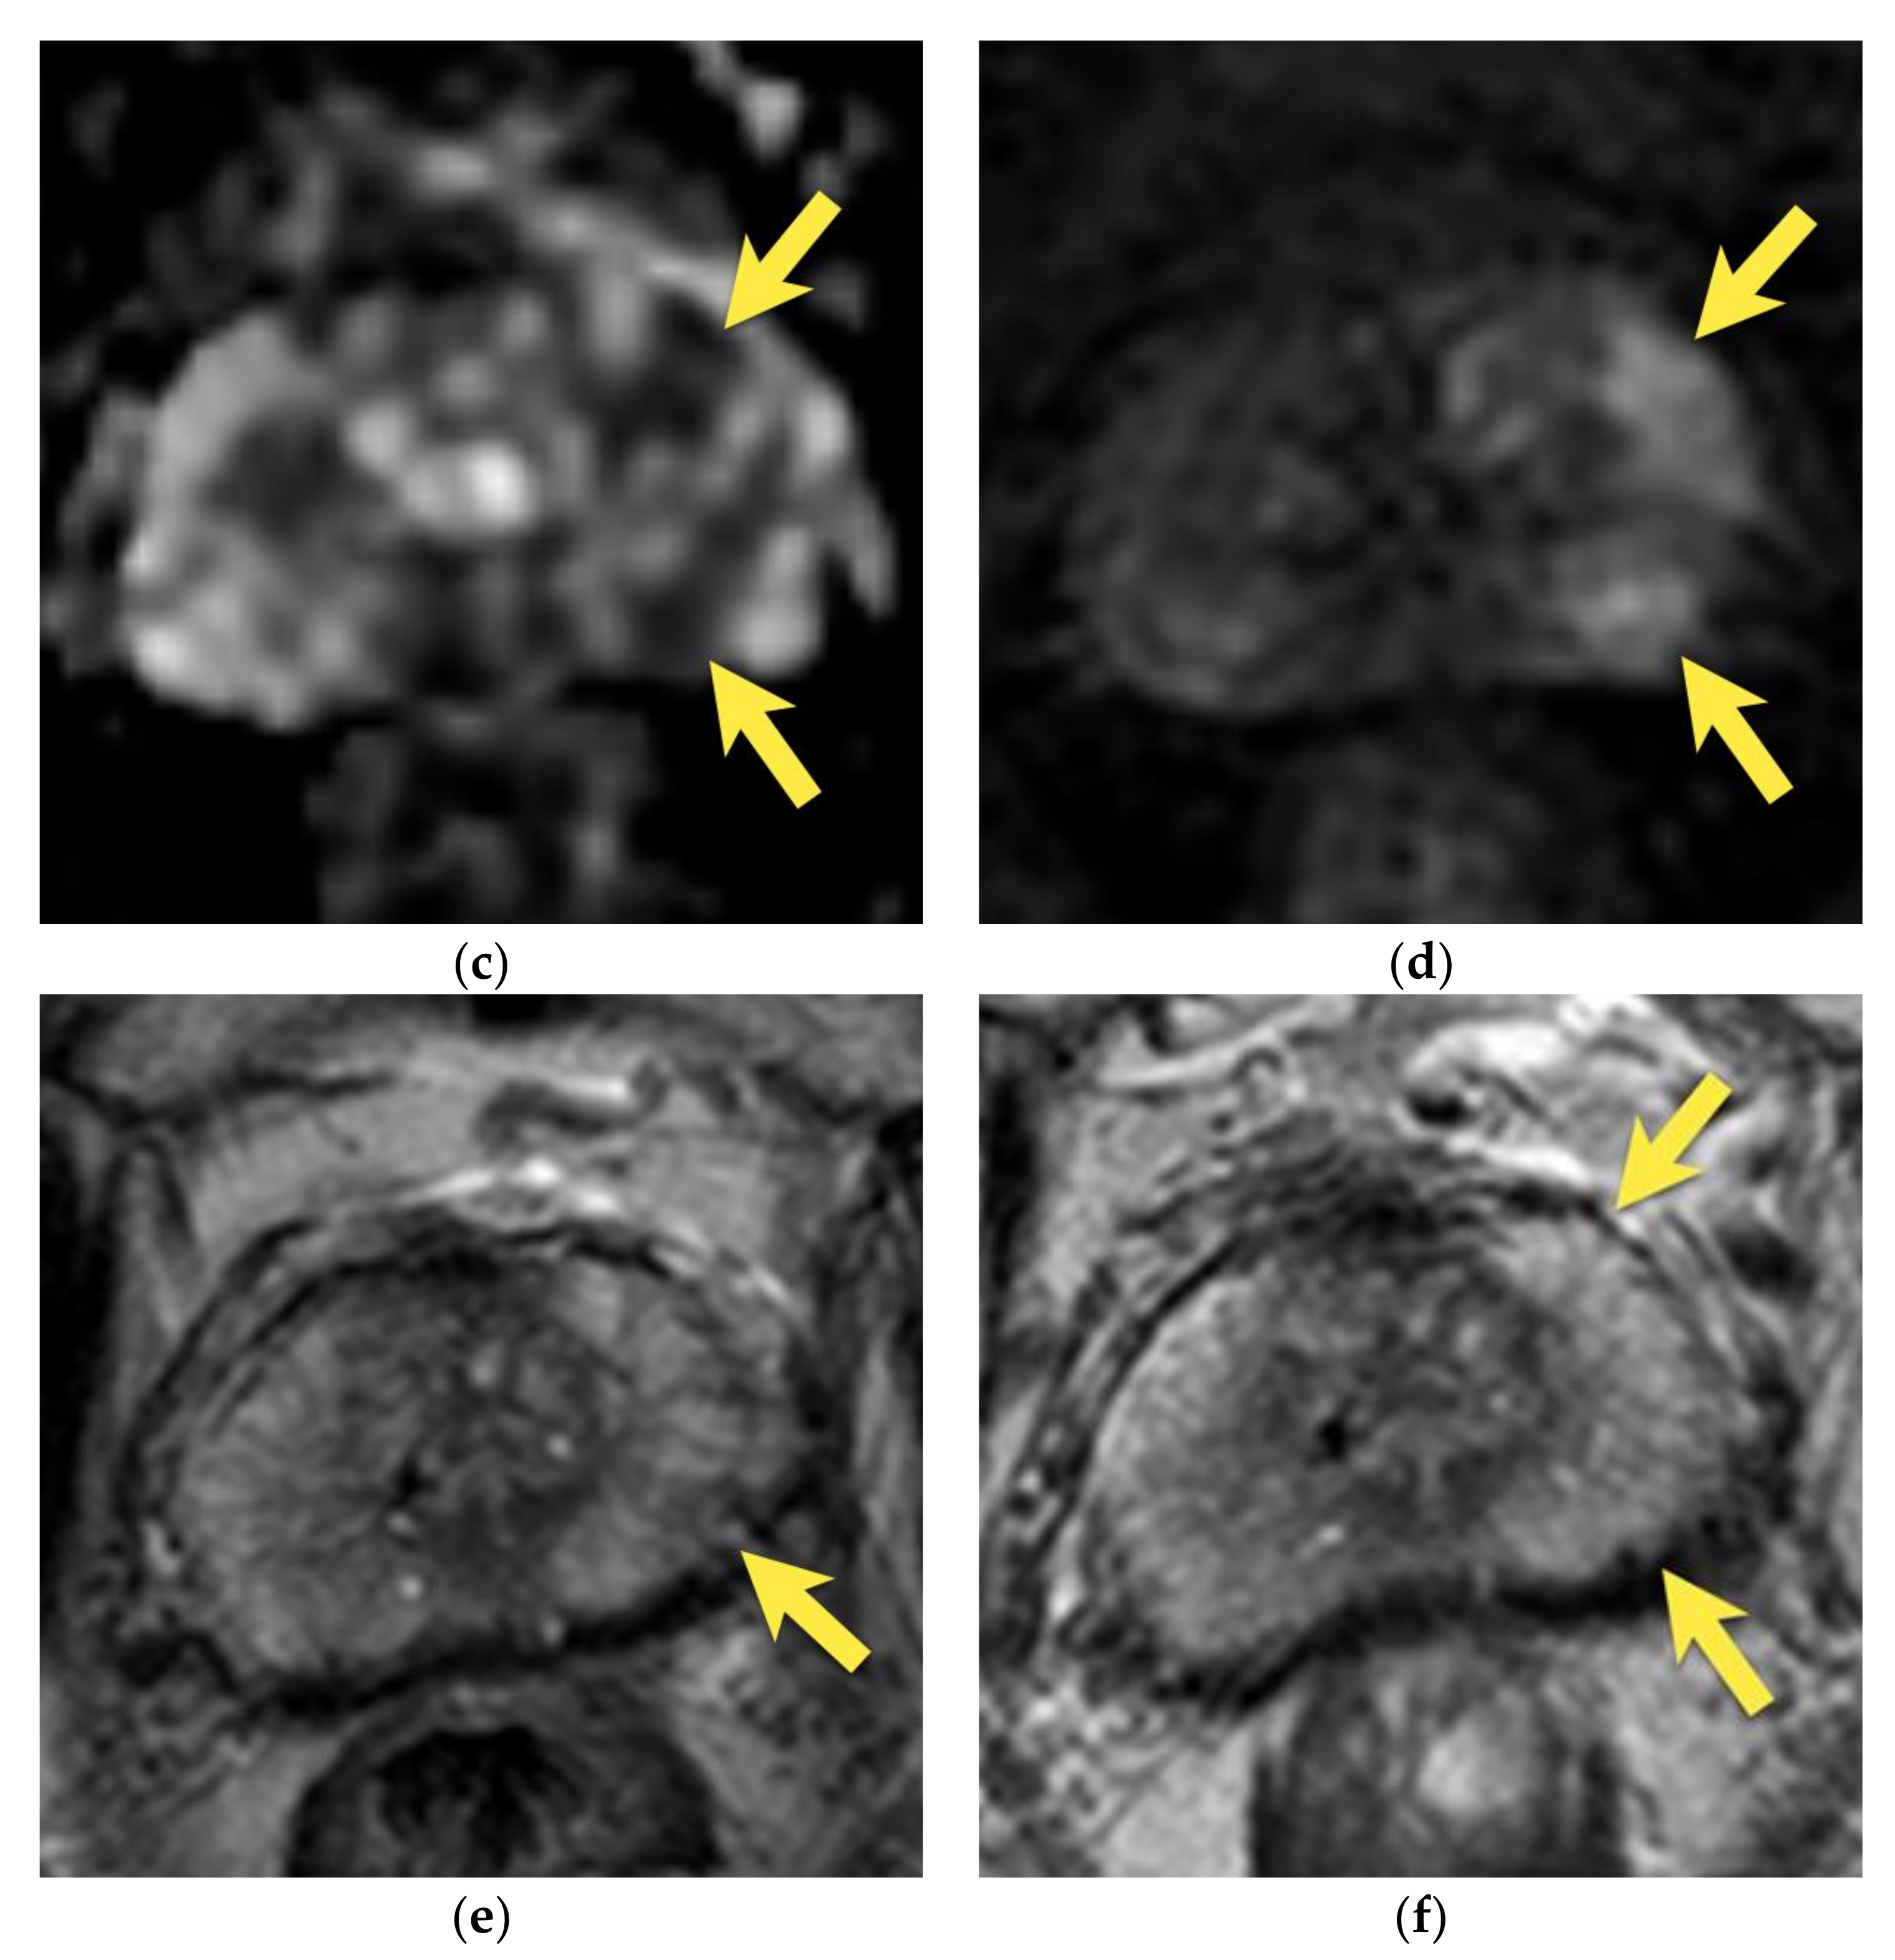

9. Prostatitis

11. Quality of Images